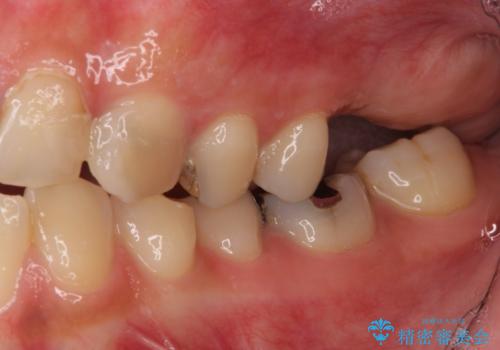

左上の欠損部はインプラントを埋入した上で補綴することとしました。

インプラント部は治癒待ちの期間が長くなるため、その期間を利用して下顎の叢生を解消し、より理想的な咬み合わせで補綴治療を行うこととしました。

下顎前歯の歯列を整えたことで、上顎前歯の咬み合わせが安定し、自然な口元に仕上げることができました。